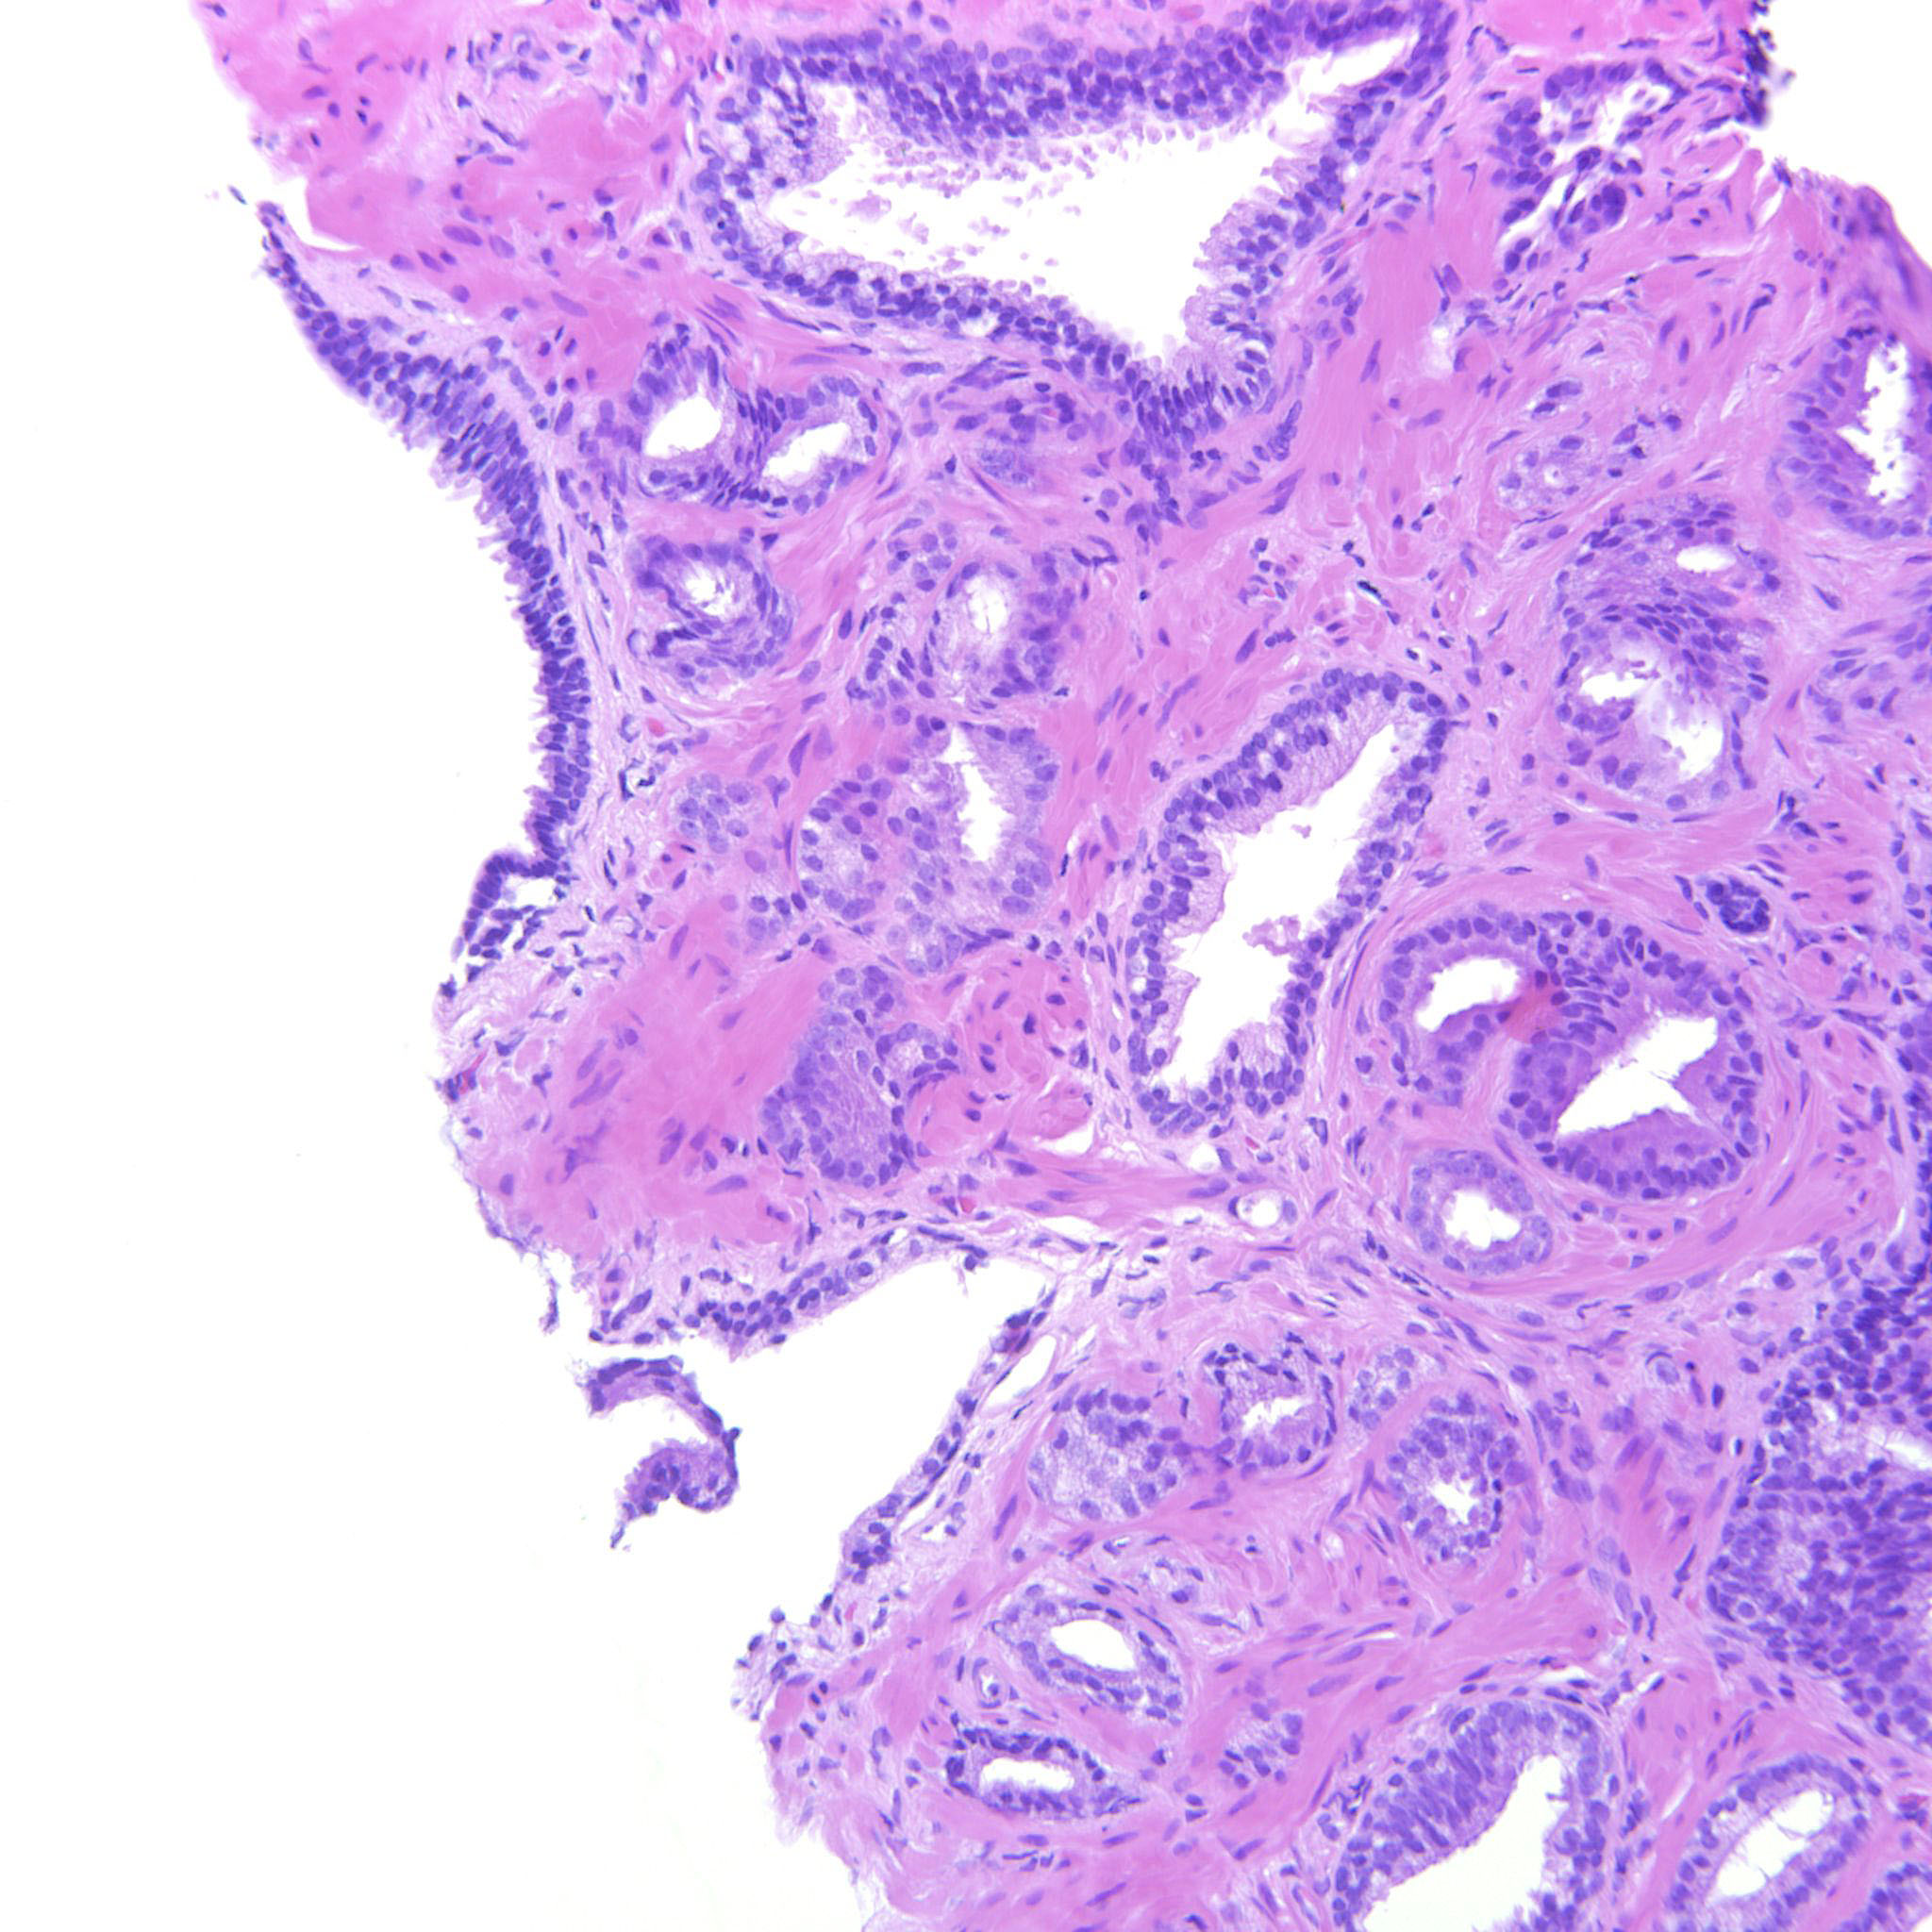

Prostate cancer grading

Case ID: 314